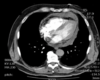

TC ventana mediastínica

A

Permite diferenciar las estructuras mediastínicas entre sí, pero el parénquima pulmonar aparece todo negro, sin apenas trama broncovascular.